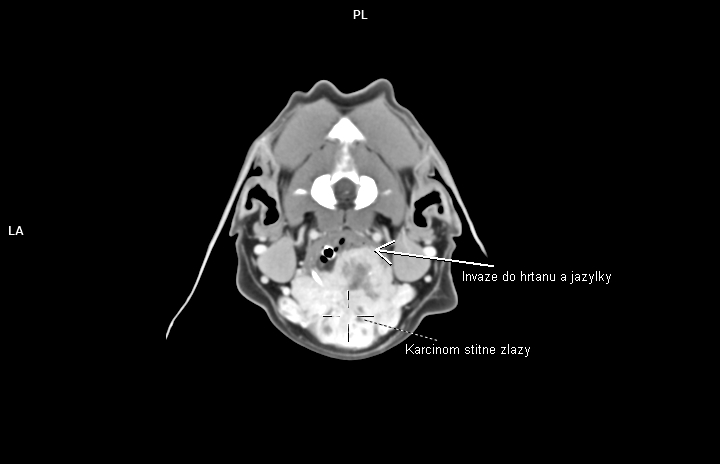

V regionu hrtanu jednoznačně vedou nádory štítné žlázy(thyreoidey). Často se jedná o zhoubné varianty (karcinomy) s lokální invazivitou do struktur hrtanu a jazylky, s tendencí k tvorbě metastáz-mediastinum, plíce. Patří ale zároveň k nádorům poměrně často operovatelným. CT pak hraje v takovýchto případech zásadní diagnostickou roli.